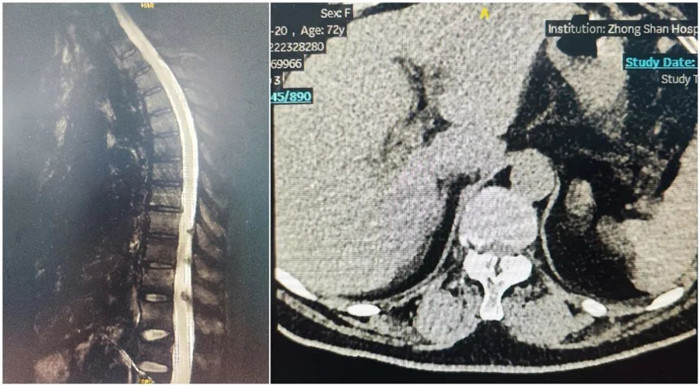

病例一

患者:女性,73歲

術(shù)式:胸腰椎椎間融合+椎板減壓+椎管擴大成型+脊髓和神經(jīng)根粘連松解術(shù)

患者兩年前出現(xiàn)左側(cè)胸背部皮膚感覺麻木,有束帶感,左上臂皮膚感覺麻木,否認肌力減退,胸平掃椎CT示:胸椎序列正常,生理彎曲存在,椎體邊緣骨質(zhì)增生,椎間盤略退變,T7-T9黃韌帶增生并伴骨化,壓迫內(nèi)膜囊,椎管狹窄。影像診斷:黃韌帶骨化。

術(shù)前影像